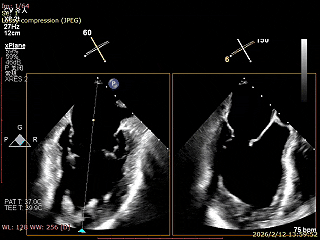

二尖瓣三维视图

2区彩色血流